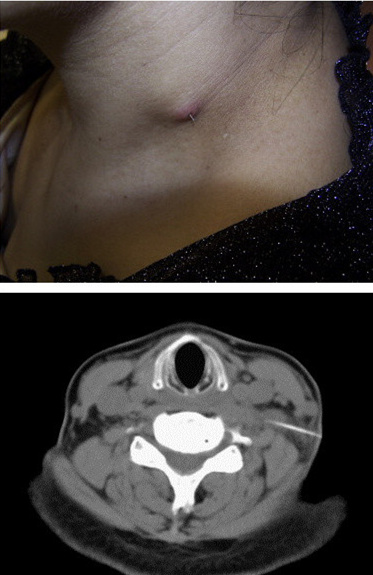

【案例四】:鱼刺穿出脖子: